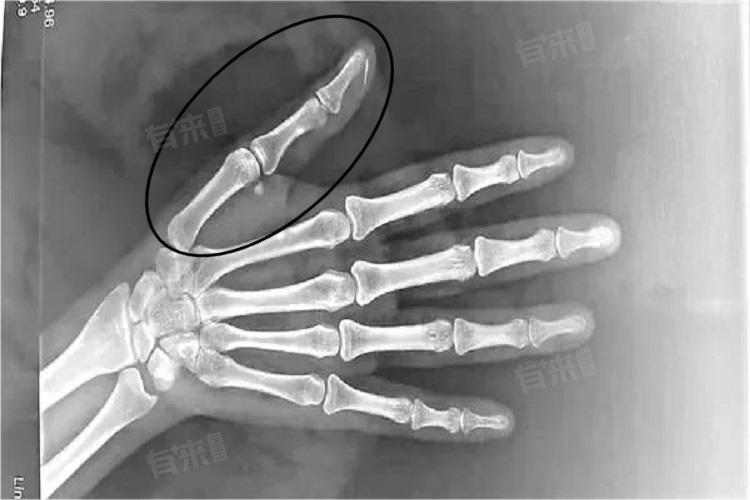

- 骨折:较为严重的外力作用可能会导致大拇指关节骨折,骨折会带来剧烈的疼痛,关节处可能出现畸形、肿胀明显,活动受限。